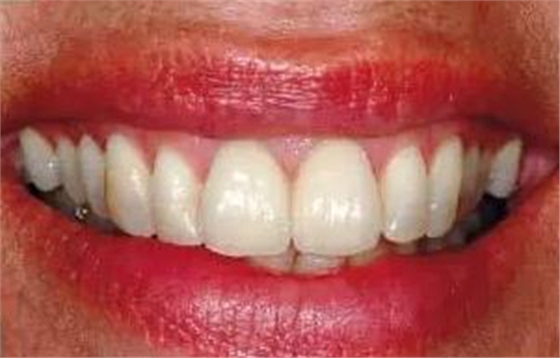

圖15、種植體植入后12個月的微笑相。